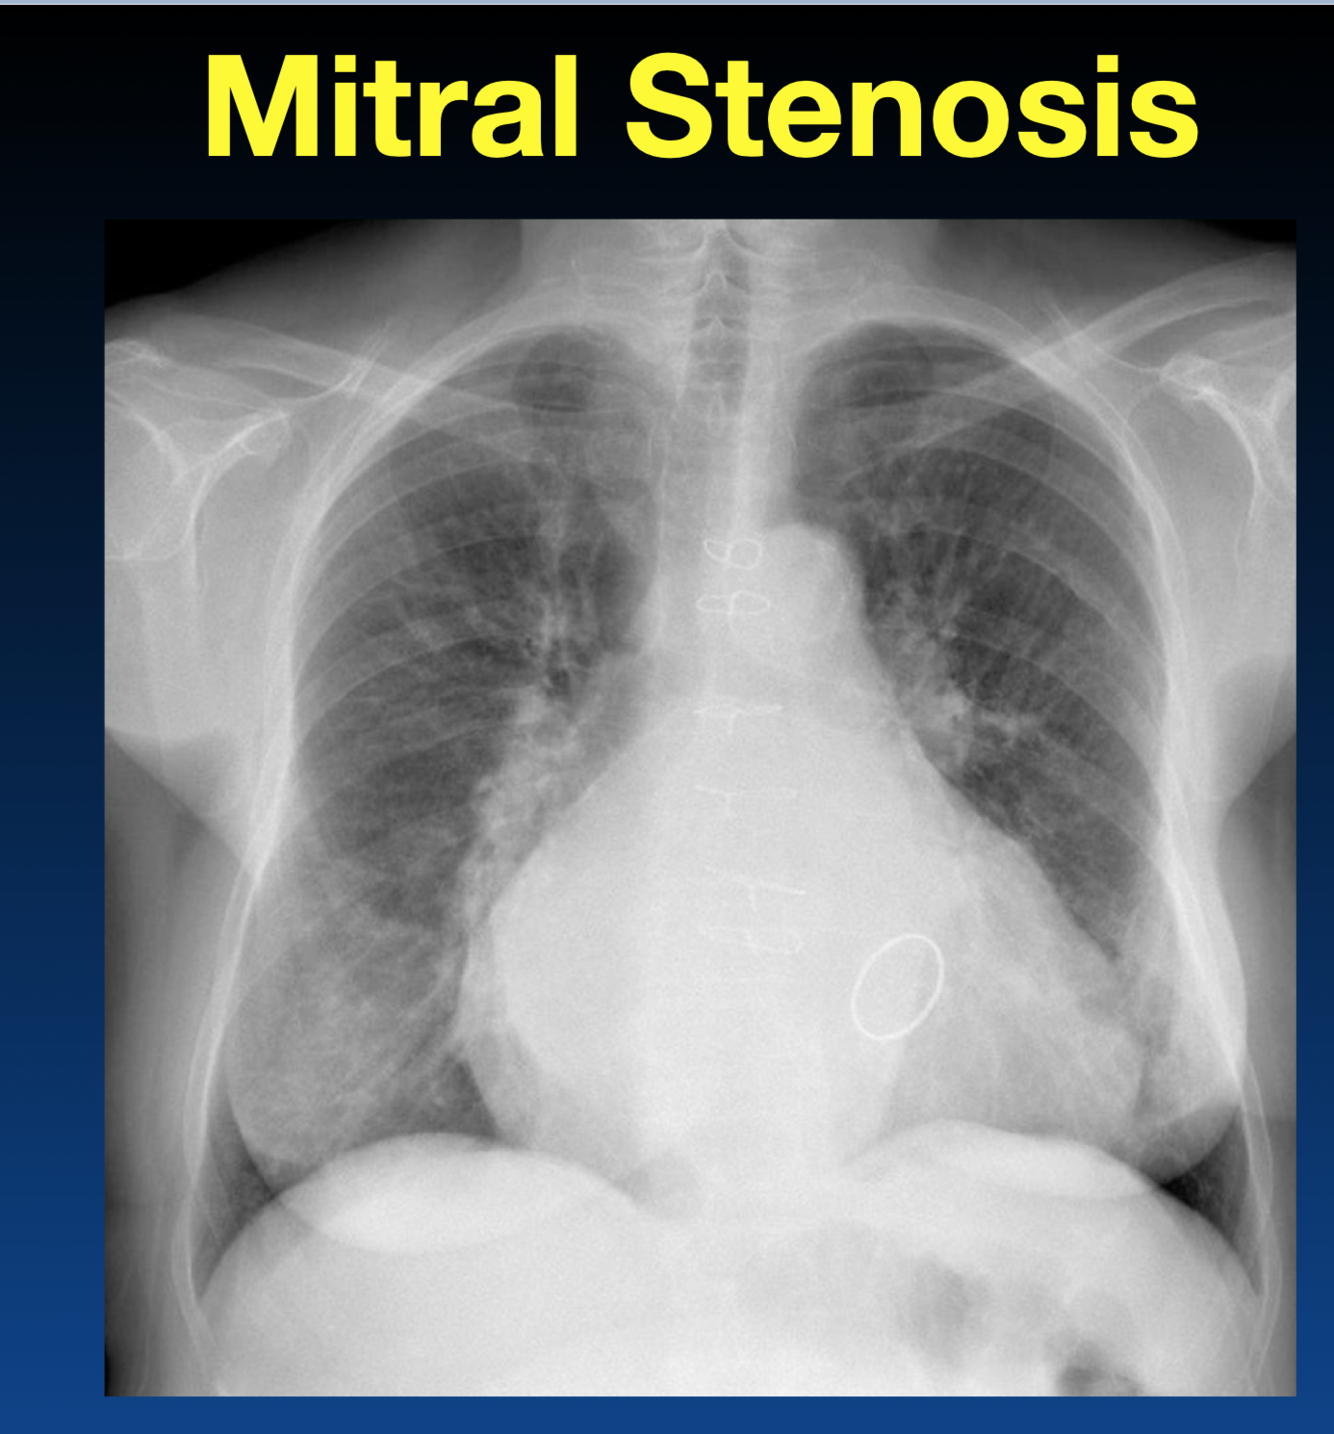

What is left atrial appendage enlargement usually indicative of?

Rheumatic Disease